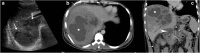

Objectives: We aim to illustrate the multimodal imaging spectrum of hepatic involvement in tuberculosis (TB). Whilst disseminated tuberculosis on imaging typically manifests as multiple small nodular lesions scattered in the liver parenchyma, isolated hepatic tuberculosis remains a rare and intriguing entity.

Methods: Indubitably, imaging is the mainstay for detection of tubercular hepatic lesions which display a broad spectrum of imaging manifestations on different modalities. While sonography and computed tomography (CT) findings have been described in some detail, there is a paucity of literature on magnetic resonance imaging (MRI) features. Due to a significant overlap with other commoner and similar appearing hepatic lesions, hepatic tuberculosis is often either misdiagnosed or labelled as indeterminate lesions. This article is a compendium of cases highlighting the spectrum of imaging patterns that can be encountered in patients with isolated primary hepatic tuberculosis as well as disseminated (secondary) disease. Rare patterns of primary disease such as tubercular cholangitis, hypervascular liver masses, and those with vascular complications are also illustrated and discussed.

Teaching points: • Hepatic TB has myriad imaging manifestations and is often confounded with neoplastic lesions. • Imaging patterns include miliary TB, macronodular TB, serohepatic TB and tubercular cholangitis. • Concurrent splenic, nodal or pulmonary involvements are helpful pointers towards the diagnosis. • Miliary calcifications along the bile ducts are characteristic of tubercular cholangitis. • Histological/microbiological confirmation is often necessary to confirm the diagnosis.